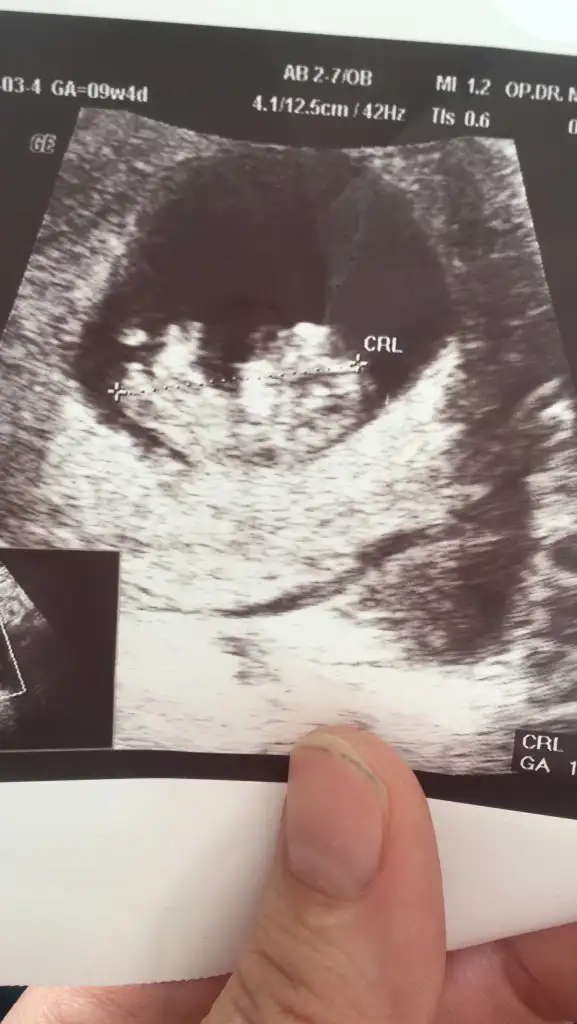

Yüzde yüz erkek derimBanada bakın sizce kız mı erkek miikinci gebeliğim aslında doktor dedi ama değişebilir dedi bir bakın lütfen

Cnm sen ne zaman gidicen. Ben geçen gun gittum başka doktora oda kız dedi ha bide bende çok baktim araştırdım erkej bebek kesesi çoğunlukla yuvarlakYüzde yüz erkek derim

Erkek bebekBanada bakın sizce kız mı erkek miikinci gebeliğim aslında doktor dedi ama değişebilir dedi bir bakın lütfen

Bence de erkek canım. Allah gonlundekini sağlıkla nasip etsinBanada bakın sizce kız mı erkek miikinci gebeliğim aslında doktor dedi ama değişebilir dedi bir bakın lütfen

Saolun amin gönlümden geçen erkek Allah elini ayağını sağ etsin bir kızım var birde paşam olsun istiyor insnaBence de erkek canım. Allah gonlundekini sağlıkla nasip etsin